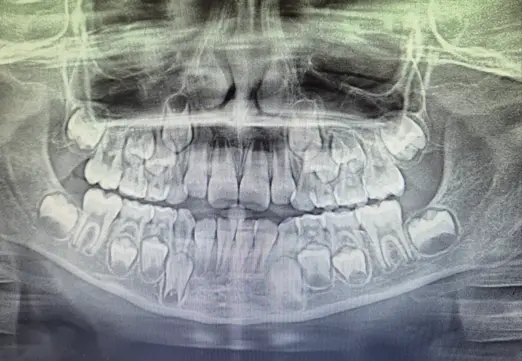

W wieku 6–8 lat często zaczyna się intensywna wymiana zębów – to dobry czas, by wykonać pantomogram i sprawdzić czy rozwój przebiega prawidłowo.

Na pantomogramie w tym wieku często widać coś, co rodzice nazywają „kosmicznym obrazem” – obok zębów mlecznych są już zawiązki zębów stałych, więc na zdjęciu potrafią pojawić się nawet cztery „rzędy” zębów. To normalne i bardzo pomocne diagnostycznie, bo pozwala ocenić, czy wszystkie zęby mają swoje zawiązki, czy wyrzynają się w dobrym kierunku i czy w łuku jest dla nich miejsce.

To także moment, w którym można ocenić, czy warto wcześnie popracować nad poszerzeniem szczęki lub żuchwy oraz czy aparat ruchomy (np. płytka) pomoże zapobiec większym problemom w przyszłości.